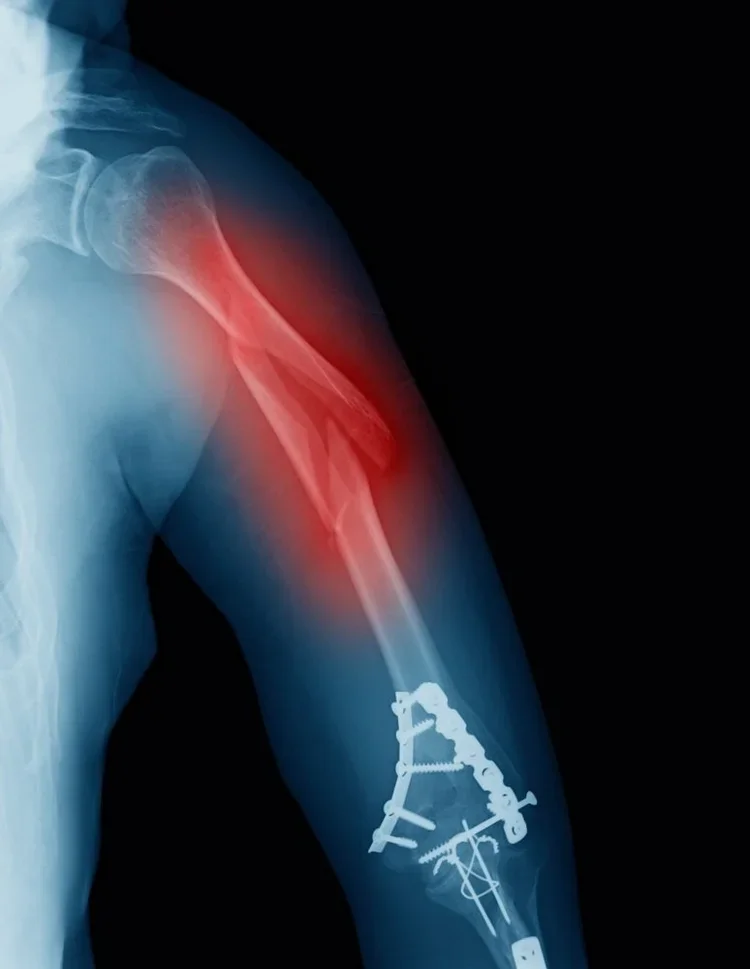

Lower Extremity Fractures

Lower extremity long bone fractures **

Select proximal femur fractures **

Distal femur fractures **

Proximal tibia fractures **

Select foot fractures

Upper Extremity Fractures

Clavicle fractures

Upper extremity long bone fractures **

Proximal humerus fractures **